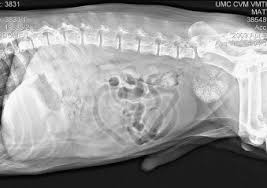

10 Signs Of Cancer In Dogs from www.pethealthnetwork.com A biopsy may also be suggested, where a sample of the tumour or an aspirate of cells or tissue is taken and examined to look for cancerous changes. Secreted by epithelial cells of stomac and duodenum. Early detection of cancer in your dog makes all the difference. Lots of other things can cause each and every one of these signs. There were no warning signs, she added, as we discussed the biopsy results after removing a cancerous mass in the intestine. Is your dog limping, walking, or playing differently melanoma in dogs can be particularly aggressive, spreading from the skin deep into a dog's organs. It can originate in the lymph nodes, bone marrow, or organs like the spleen. Although it might be somewhat less common compared to gastrointestinal tumors, for example, this type of cancer is still possible and can be encountered in.

When should you take your dog to the vet? Do you know the signs of cancer in dogs? For example, signs of skin cancer in dogs largely differ from those that indicate the possibility of your pet having stomach cancer. She had no other signs of cancer other than that little bit of blood. Some lumps are benign, meaning not cancer. Symptoms of canine cancer vary, but any observed lump should be taken seriously. However, being oriented with the signs discussed above will greatly help in the early diagnosis of canine cancers. Vets talk about the signs of cancer in dogs. But the fact is that one in three dogs will eventually develop some form of cancer during their that's why it's so important to learn the most common signs of cancer in dogs. Any time you have an inbred population, you don't know what else is being inherited along with the. Gastrointestinal neoplasia is cancer located anywhere throughout the gastrointestinal (gi) tract, including with gastrointestinal cancer, clinical signs are largely dependent on the location of the cancer diagnosis of gastrointestinal neoplasia in dogs. It is important to note that any of these problems can be a sign of a variety of illnesses and do not automatically indicate that your dog has cancer. Cancer is the leading cause of death in dogs.

Cancer in dogs can be quite common for those aged over 10. There were no warning signs, she added, as we discussed the biopsy results after removing a cancerous mass in the intestine. Unfortunately, cancer in dogs is relatively common, especially in dogs older. Any part of the body can become cancerous, such as soft tissue, nerves, bone, or even fluids such as blood or the white cells that fight infection. Signs of nasal cancer in dogs are abnormal discharge, bleeding, snoring or trouble breathing.

Another sign of cancer in dogs you'll want to be watching out for are changes in behavior. A diagnosis of cancer in a beloved dog can be heartbreaking for any owner. Early detection really is key to fighting cancer in dogs, said carol mcconnell, dvm, mba, nationwide's chief veterinary officer. Cancer is a topic that no pet parent wants to think about. Your vet can ascertain whether the weight loss is related to a cancerous growth or to some other cause and can suggest a course of treatment. The warning signs of cancer in dogs are very similar to that in people. Any time you have an inbred population, you don't know what else is being inherited along with the. For example, a bone tumor (osteosarcoma) might cause a limp, or a bladder tumor the good news is, not all of these signs point to cancer. If you see lumps on your pet, your veterinarian can take a few. Chronic gastrointestinal problems such as vomiting and diarrhea can be symptoms of cancer of the gi tract. Vets talk about the signs of cancer in dogs. Is your dog limping, walking, or playing differently melanoma in dogs can be particularly aggressive, spreading from the skin deep into a dog's organs. Problems with eating or swallowing are a common result of cancers in the mouth and neck.